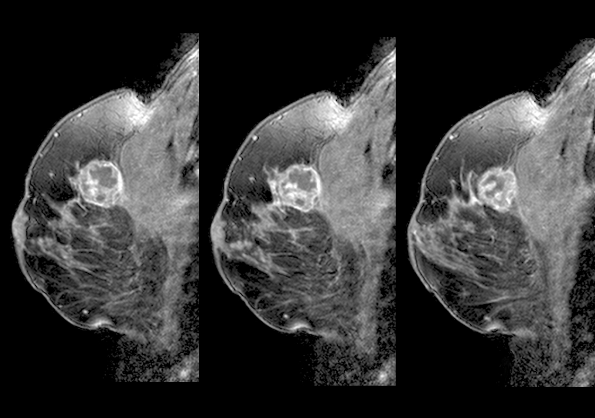

전이성 유방암 진단은 초기 유방암과는 다르게, 이미 암이 다른 장기로 퍼진 상태이기 때문에 더 철저하고 다양한 검사 방법이 필요해요. CT, MRI, PET-CT와 같은 첨단 영상 진단 기술을 이용하여 전이된 암의 위치와 크기, 그리고 암세포의 특성을 파악하는 것이 중요해요.

이러한 정보들은 치료 계획을 세우는 데 있어서 매우 중요한 기초 자료가 되죠. 정확한 진단은 최적의 치료 방법을 결정짓는 첫걸음이며, 환자의 생존율 향상에 결정적인 요소가 되는 만큼, 정밀한 진단 절차에 대해 이해하고, 적극적으로 참여하는 것이 매우 중요하답니다.